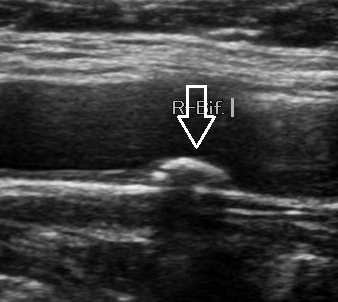

경동맥 초음파의 가장 대표적인 산출물은 플라크 유무, 위치(분지부/내경동맥/총경동맥), 크기, 표면 상태, 석회화 여부입니다. 플라크는 단순히 “있다/없다”가 아니라,

• 플라크가 여러 개로 산재했는지(다발성)

• 표면이 매끈한지, 울퉁불퉁한지(불안정성 추정)

• 석회화가 동반되는지(만성 변화 가능성)

• 혈류를 의미 있게 방해하는지(협착률과 속도 상승)

같은 요소를 함께 봐야 합니다. 특히 플라크가 있다는 사실 자체가 전신 동맥경화가 진행 중이라는 의미로 해석되는 경우가 많아서, 심장(관상동맥)과 뇌혈관 위험 관리의 “경고등” 역할을 합니다.